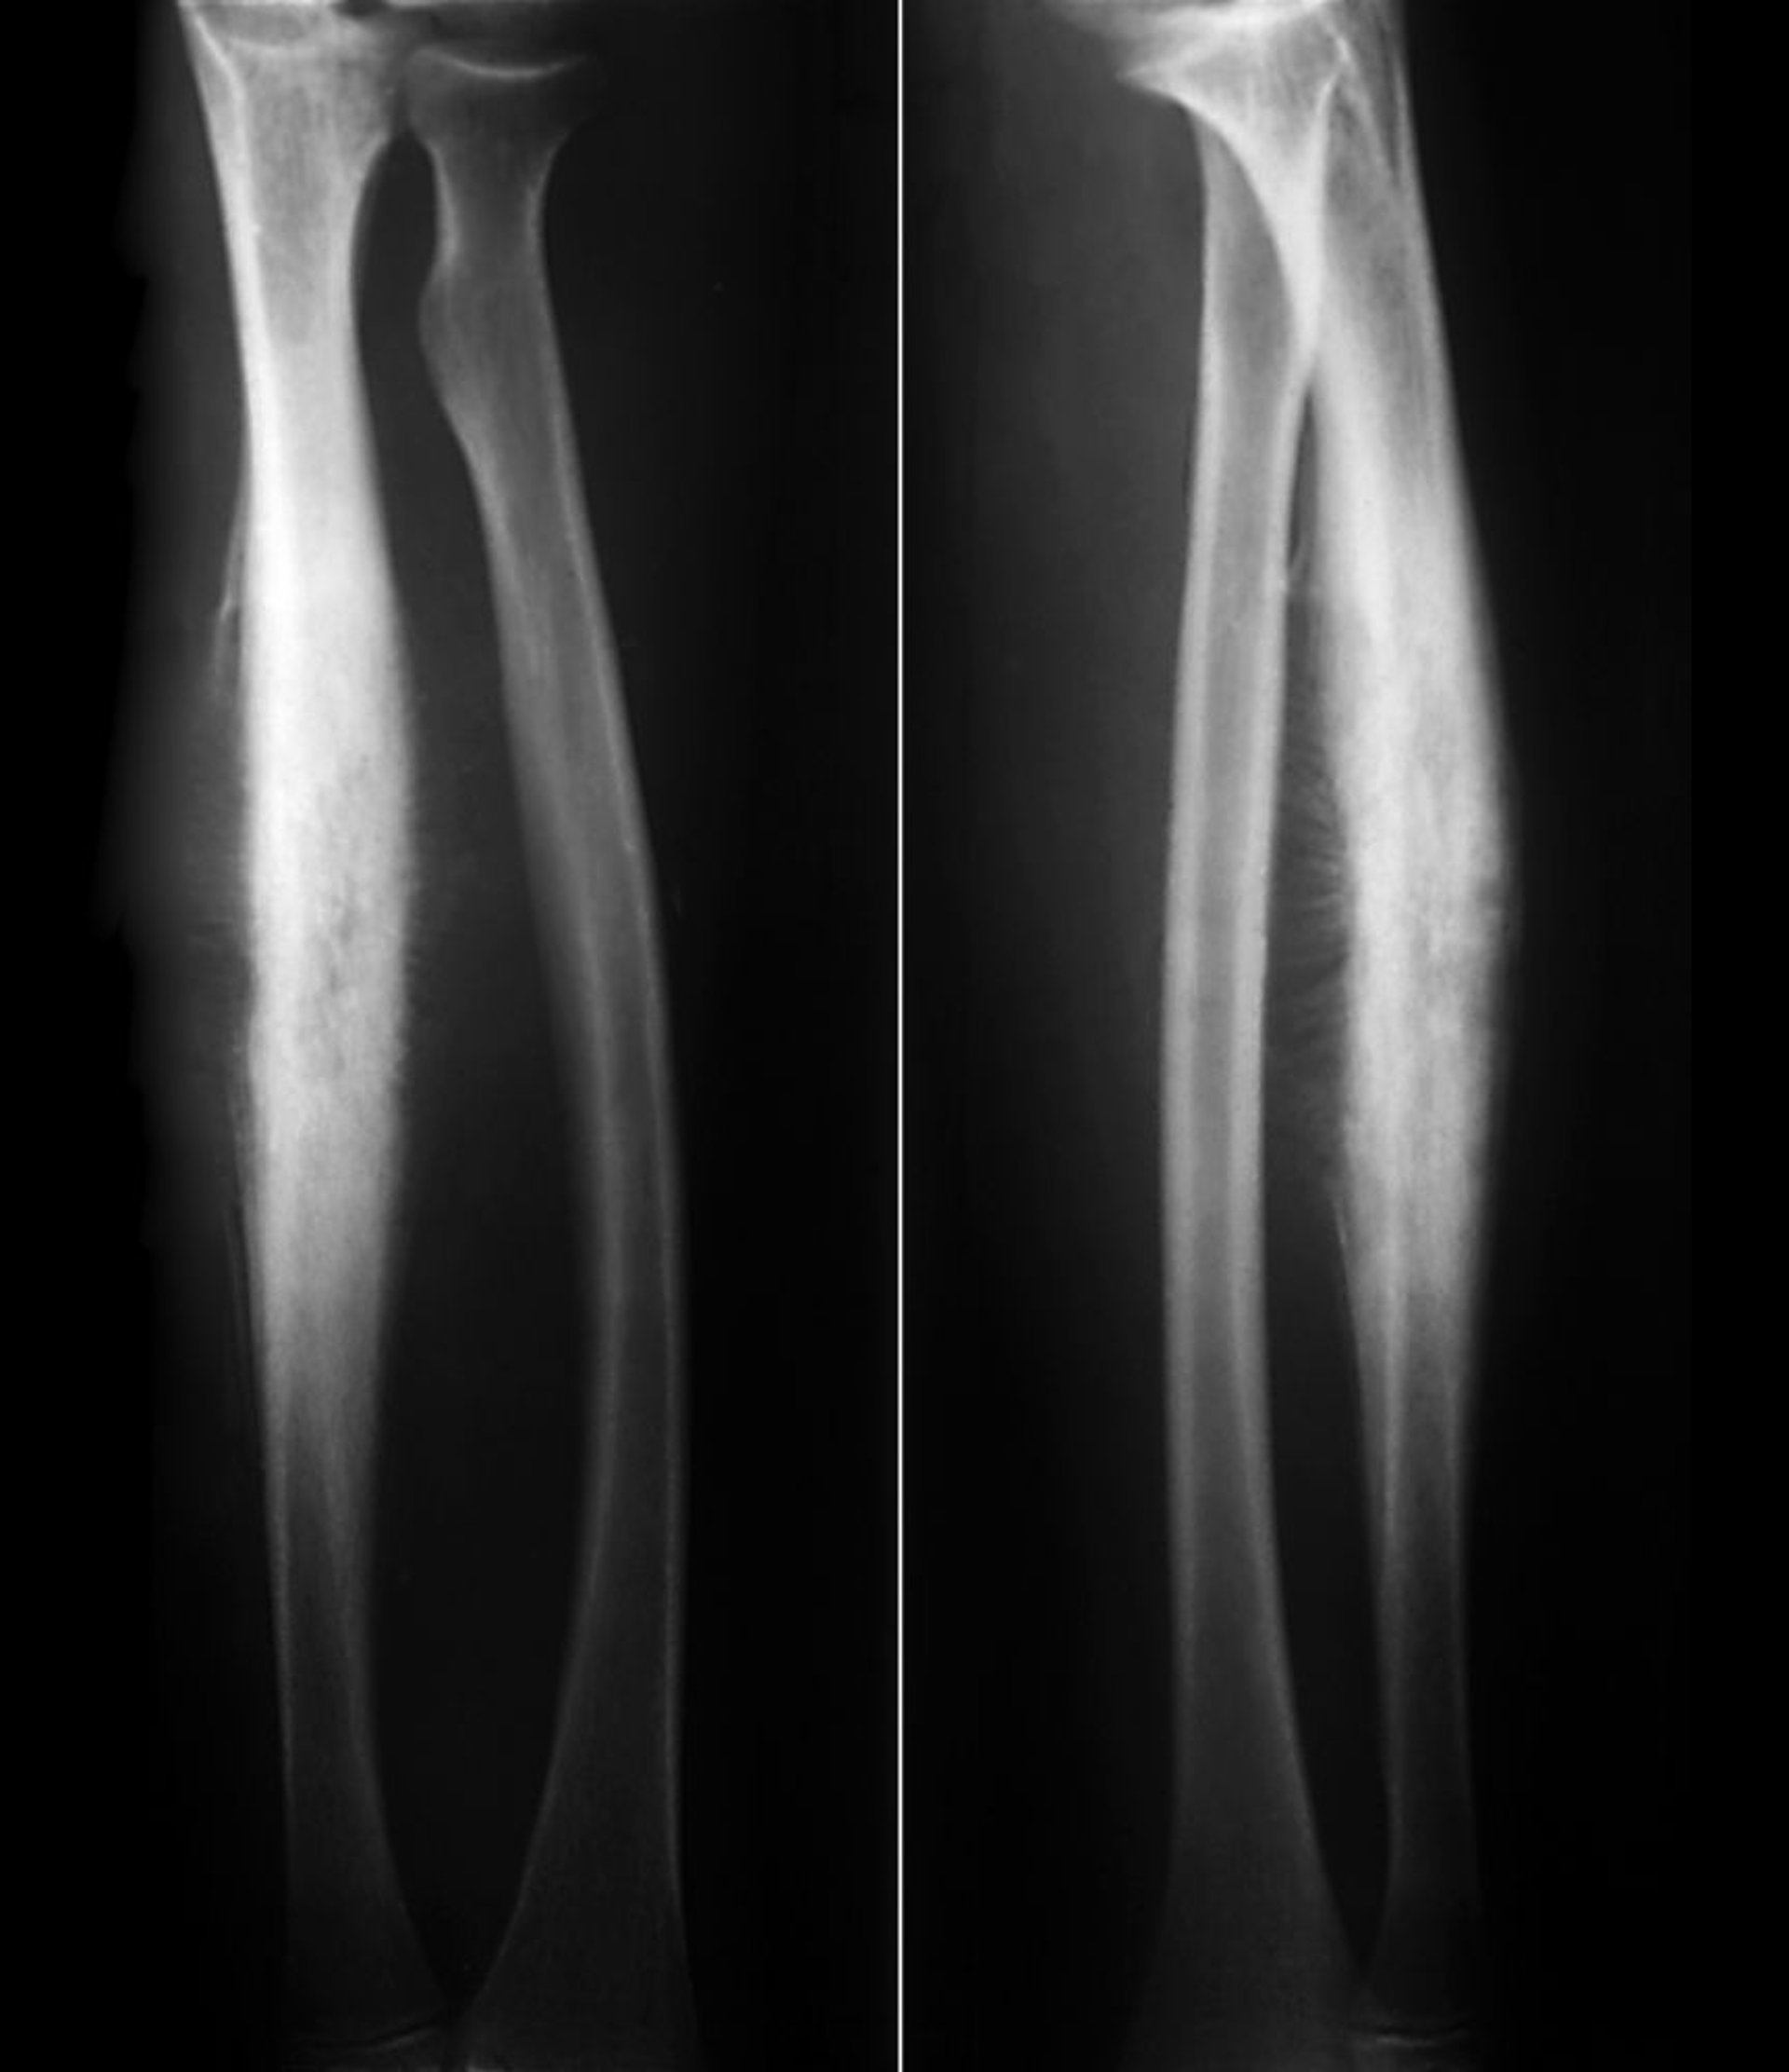

Sarcoma di Ewing del radio

Questo sarcoma di Ewing della diafisi radiale mostra una neoformazione ossea reattiva subperiostale in una classica reazione periostale "a raggiera" insieme alla distruzione litica dell'osso corticale.

ZEPHYR/SCIENCE PHOTO LIBRARY